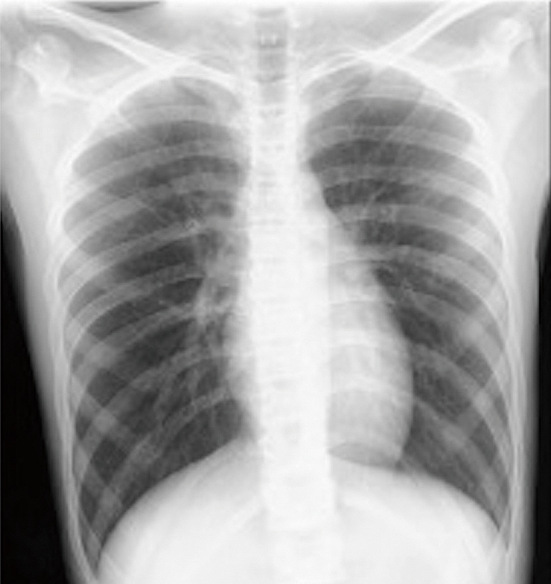

Coronavirus disease 2019 (COVID-19)-related intracranial hemorrhage (ICH) is believed to be associated with at least one known risk factor for ICH, such as hypertension, hyperlipidemia, diabetes mellitus, severe pneumonia, or anticoagulation therapy. However, in this study, we report a case of ICH in a 14-year-old boy with mild COVID-19 infection without pneumonia who had no such risk factors. The only abnormal laboratory finding was temporary depletion of vitamin K-dependent coagulation factors. This case indicates that COVID-19 infection may cause simultaneous asymptomatic intracranial microhemorrhages and temporary depletion of vitamin K-dependent coagulation factors. This temporary depletion might transform the intracranial microhemorrhages into symptomatic ICH.

与冠状病毒病 2019(COVID-19)相关的颅内出血(ICH)被认为至少与一个已知的 ICH 危险因素有关,如高血压、高脂血症、糖尿病、重症肺炎或抗凝治疗。然而,在本研究中,我们报告了一例 ICH 病例,患者是一名 14 岁男孩,患有轻度 COVID-19 感染,无肺炎,且无上述危险因素。唯一的实验室异常发现是维生素 K 依赖性凝血因子的暂时性耗竭。该病例表明,COVID-19 感染可能同时导致无症状性颅内微出血和维生素 K 依赖性凝血因子的暂时性耗竭。这种暂时性消耗可能会将颅内微出血转变为有症状的 ICH。